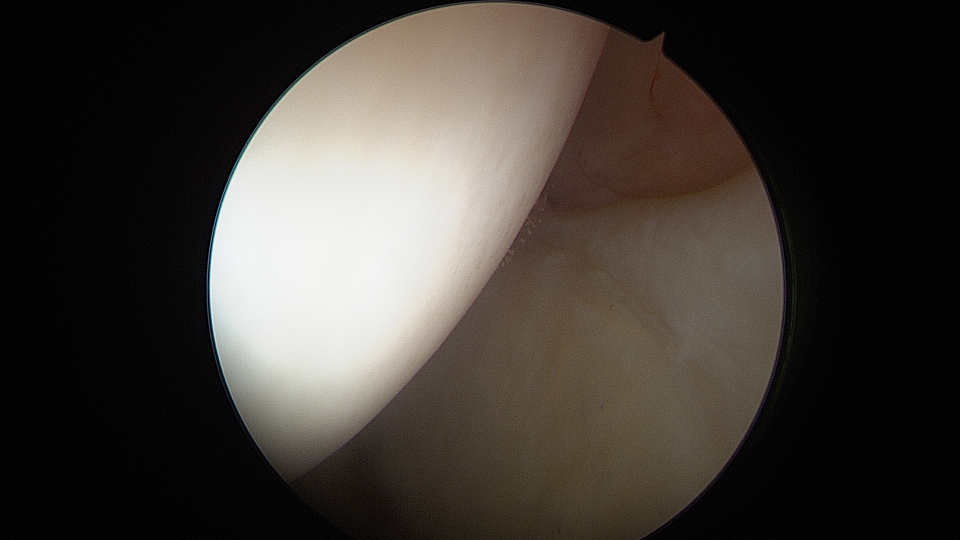

Η έγχυση στο ισχίο, αποτελεί μία καθιερωμένη τεχνική στα πλαίσια της συντηρητικής αντιμετώπισης της μηροκοτυλιαίας πρόσκρουσης. Παραδοσιακά, η λήψη απόφασης για αρθροσκόπηση ισχίου επηρεάζεται σε μεγάλο βαθμό από την ανταπόκριση του ασθενή στην έγχυση. Νέα μελέτη, όμως, έδειξε ότι το αποτέλεσμα της αρθροσκόπησης ισχίου δεν συναρτάται πάντα με το αποτέλεσμα της έγχυσης αυτής.

Σε μία νέα μελέτη, έγινε προσπάθεια να προσδιοριστεί η διαφορά του αποτελέσματος μετά από αρθροσκόπηση ισχίου, σε ασθενείς που ανταποκρίθηκαν, και σε αυτούς που δεν ανταποκρίθηκαν μετά από έγχυση ισχίου με στεροειδές.

Επρόκειτο για μία αναδρομική μελέτη ασθενών που υπεβλήθησαν σε πρωτογενή αρθροσκόπηση ισχίου, μεταξύ των ετών 2012 και 2014.  Οι ασθενείς χωρίστηκαν σε δύο ομάδες, με την πρώτη να αποτελείται από αυτούς που ανταποκρίθηκαν θετικά στην έγχυση, και τη δεύτερη, από αυτούς που δεν ανταποκρίθηκαν τελικά.  Για την εκτίμηση των αποτελεσμάτων χρησιμοποιήθηκαν οι συνήθεις κλίμακες αξιολόγησης του ισχίου. Συμπεριελήφθησαν 116 ασθενείς από την κάθε ομάδα, και έγινε επεξεργασία των αποτελεσμάτων με στατιστικές μεθόδους.  Δεν υπήρχαν διαφορές σχετικά με τα δημογραφικά, και άλλα γενικά στοιχεία των δύο ομάδων. Παρατηρήθηκε ότι και οι δύο ομάδες παρουσίασαν παρόμοια αποτελέσματα, μετά από την αρθροσκόπηση ισχίου, σε χρονικό διάστημα 10 ετών.

Οι συγγραφείς συμπέραναν ότι η ανταπόκριση μετά από έγχυση στο ισχίο με στεροειδές, δεν σχετίστηκε με διαφορές στα δεκαετή αποτελέσματα μετά από αρθροσκόπηση ισχίου, ή στο ποσοστό επανεγχείρησης. Έτσι, φάνηκε ότι ενώ η ενδαρθρική έγχυση στο ισχίο παραμένει ένα σημαντικό εργαλείο στην εκτίμηση της μηροκοτυλιαίας πρόσκρουσης, η έλλειψη θετικής ανταπόκρισης μετά από αυτήν δεν αποκλείει ένα θετικό αποτέλεσμα μετά από αρθροσκόπηση ισχίου.